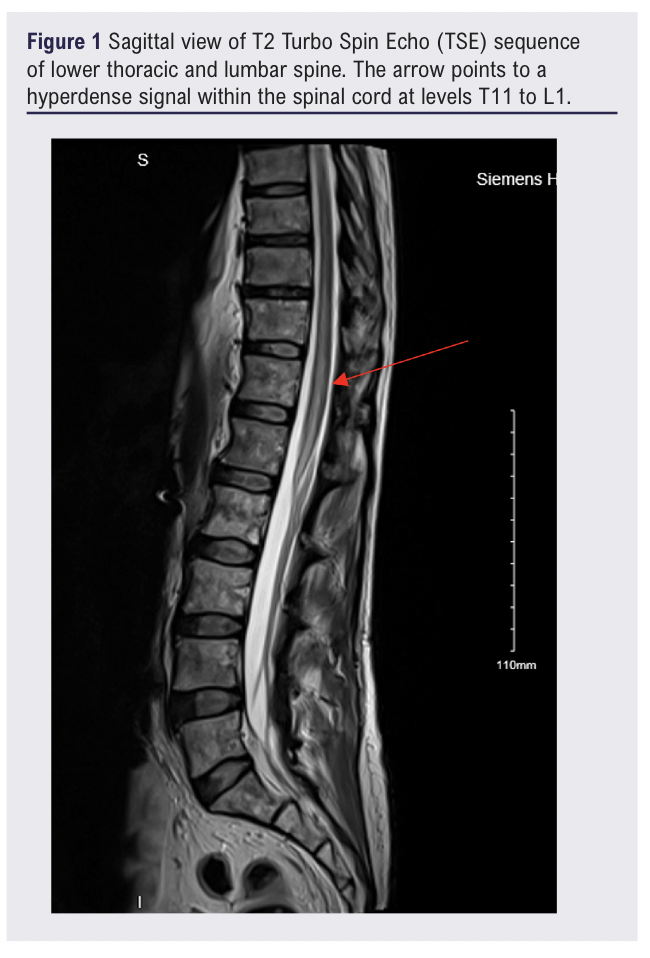

On postoperative day 4, new bilateral foot drop was noted. Neurological examination showed complete loss of power (0/5) and sensation in both lower limbs, absent reflexes and faecal incontinence. MRI on postoperative day 4 revealed acute spinal cord infarction from T11 to L1 involving the conus medullaris. This can be seen in figure 1 and figure 2. No haematoma was identified.

The neurology and haematology teams hypothesised that the spinal cord infarction was due to a paradoxical thromboembolic event in the setting of acute ITP.